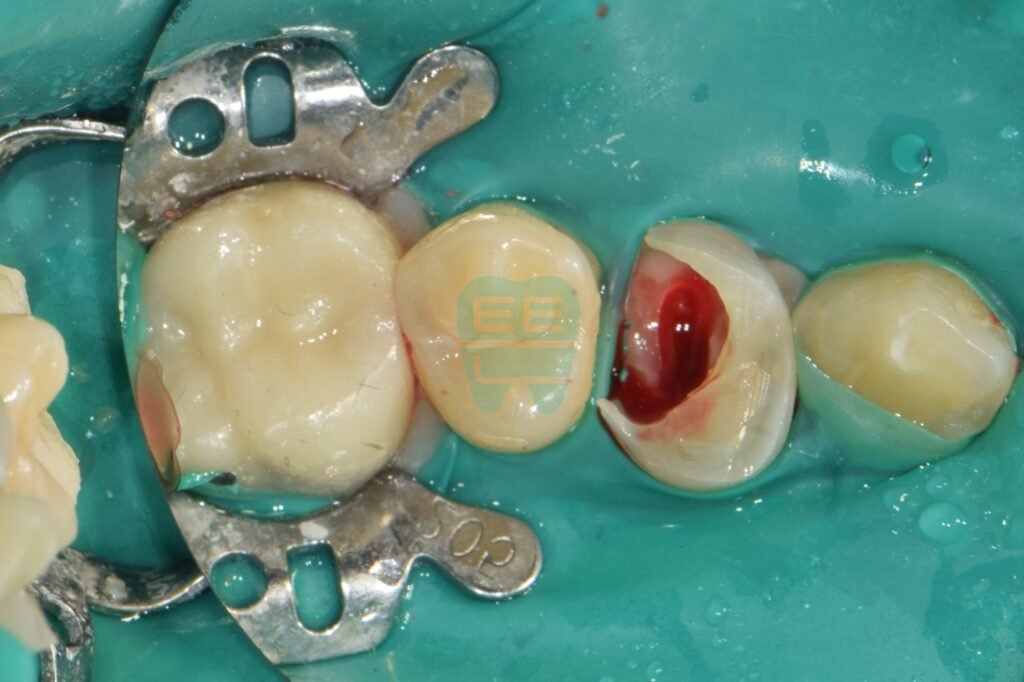

2. 잇몸 정리 및 치관 확장술 (Crown Lengthening)

치료를 하려면 먼저 ’치아의 경계’를 찾아야 합니다. 자라 들어온 잇몸을 깨끗하게 제거하고, 필요하다면 잇몸 뼈를 다듬어 치아 머리를 잇몸 위로 노출시키는 치관 확장술을 진행합니다.

잇몸을 정리하고 나니 비로소 숨어있던 치아의 뿌리와 경계 부위가 드러납니다. 이제 치료를 시작할 준비가 되었습니다.

3. 러버댐 장착 & 레진 벽(Wall) 세우기 (핵심 과정

)

이 과정이 오늘 치료의 하이라이트입니다. 신경치료(근관치료)를 하려면 소독약이 새지 않고 침이 들어가지 않도록 ‘밀폐’가 되어야 하는데, 치아 벽이 다 무너져서 불가능한 상황이었죠.

그래서 러버댐을 걸고, 무너진 치아 주변에 단단한 레진으로 가짜 벽(Wall)을 만들어줍니다.